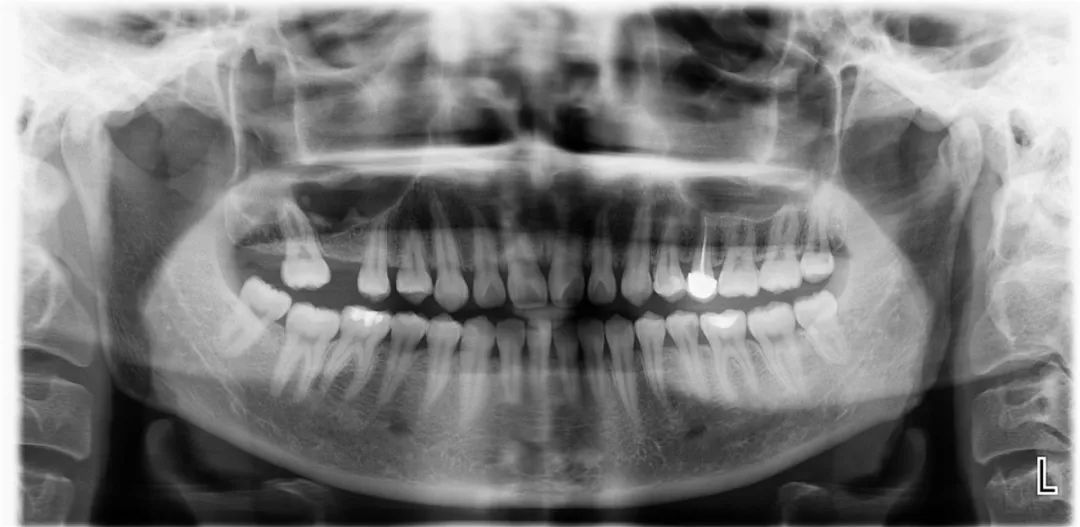

术后